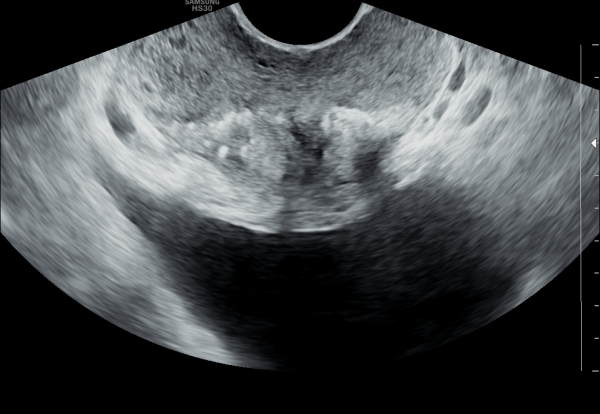

수년전부터 하복부 통증과 배뇨장애와 빈뇨와 급밥뇨가 심해 개인 비뇨기과와 상급의료기관에서 치료를 했으나 증상의 호전이 없고 최근 두달전 증상이 심해져 내원 당일 경직장 초음파 검사상 좌우 사정관 입구의 결석이 심하고 오래전부터 막혀 전립선의 이행구역과 주변 구역까지 결석이 침습된 전립선 사진입니다.

For several years, the patient had been experiencing lower abdominal pain, urinary dysfunction, frequent urination, and urgency. Despite receiving treatment at private urology clinics and tertiary medical centers, there was no improvement in symptoms. On the day of the visit, a transrectal ultrasound examination revealed severe calcification at the openings of both ejaculatory ducts. The ducts had been chronically obstructed, allowing the calcifications to invade the transition zone and surrounding areas of the prostate.